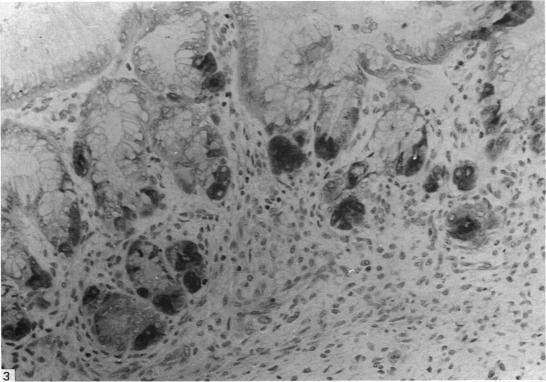

The stomachs from 15 human fetuses and 5 neonates were examined by immunocytochemical methods for the presence of intrinsic factor. Intrinsic factor was localised in cells within the gastric mucosa of all fetuses from 11 weeks of gestation onwards. The cells, which were immunoreactive for intrinsic factor, were located mainly at the base of the developing gastric glands in both the pylorus and corpus of the stomach. Occasional cells located at the isthmus of the gastric glands and amongst the surface columnar cells were strongly immunoreactive for intrinsic factor. With conventional staining these cells had the morphological and histochemical characteristics of parietal cells.

采用免疫细胞化学方法检查了15例人类胎儿和5例新生儿的胃,以检测内因子的存在。从妊娠11周起,所有胎儿胃黏膜中的细胞均检测到内因子。对内因子呈免疫反应的细胞主要位于胃幽门和胃体部发育中的胃腺底部。偶尔在胃腺峡部和表面柱状细胞之间的细胞也对内因子呈强免疫反应。用传统染色法,这些细胞具有壁细胞的形态和组织化学特征。